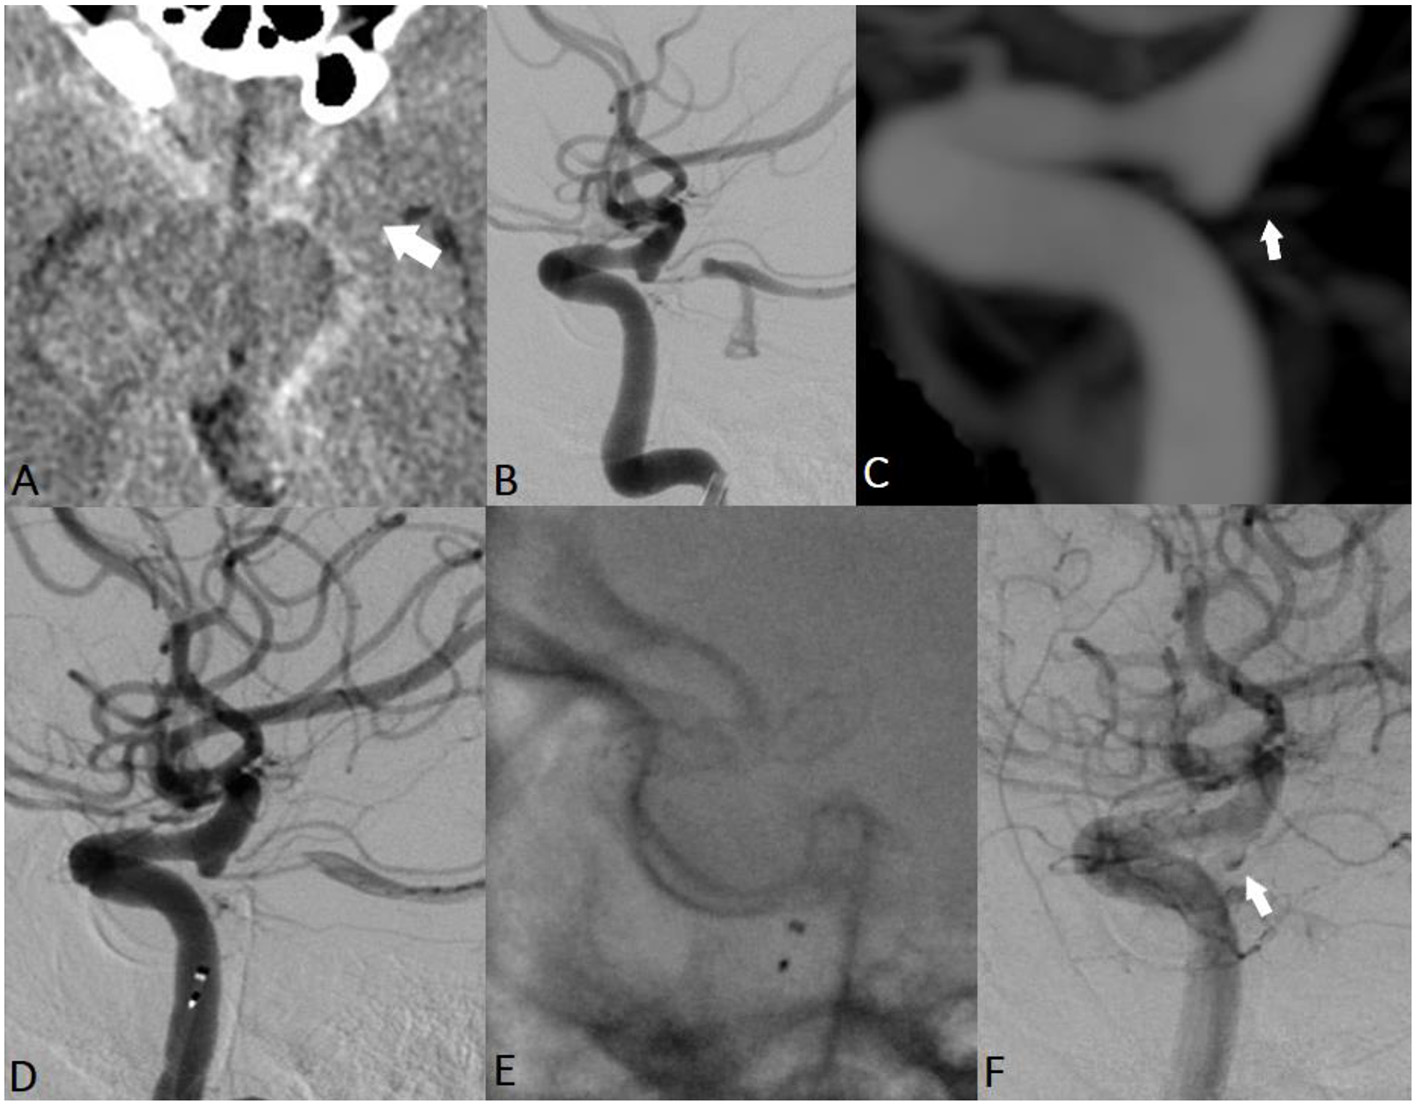

A 19-year-old woman was found unconscious at home (Figure 3). Her last memory was of an extreme burning sensation engulfing her neck and scalp. CT revealed a thin SAH mainly distributed in the left suprasellar cistern and left hemispheral subarachnoid spaces. CT cranial angiography and initial DSA did not indicate any aneurysmal dilatations or other vascular findings. Subsequently, 3DRA revealed the presence of an ID at the level of the orifice of the left ophthalmic artery. The secondary delayed DSA indicated the presence of a focal irregularity adjacent to the OA ID. The patient repeatedly reported having observed increasing flashes of light and bright spots in her left eye during this period. A ruptured OA ID was hypothesized to have been responsible for the cerebral hemorrhage, and the patient was scheduled for EVT with an FD stent. The patient was premedicated with a loading dose of DAP, and the implantation of the endoluminal flow modulation device was performed uneventfully. The patient was discharged without any related procedural complications. Follow-up angiography demonstrated no infundibular widening and the complete preservation of the OA.

Figure 3. EVT of ruptured OA ID in a young woman. The initial radiological work-up indicated intracranial hemorrhage, suggesting the rupture of an intracranial aneurysm (A; white arrow). Cranial CTA and initial DSA did not reveal any cerebrovascular pathologies that could be associated with the hemorrhage (B,C). Three-dimensional rotational angiography demonstrated the presence of an ID at the level of the orifice of the left ophthalmic artery (D; white arrow). Endovascular FD deployment was performed with complete coverage of the OA infundibular orifice (E–G).

A 60-year-old man was admitted to the hospital with severe headache, nausea, vomiting, and prominent neck stiffness (Figure 4). He reported that the headache intensity had worsened in the prior 7 days and did not respond to analgesics. CT demonstrated the presence of a diffuse SAH with a focal distribution mainly into the chiasmatic, interpeduncular, and left crural cisterns. CTA did not reveal any cerebrovascular pathology but confirmed the presence of an ID at the level of the left PcomA. The patient underwent catheter angiography, which yielded similar observations to those of the initial and delayed DSA examinations. Considering the above findings, we assumed that the most probable cause of the SAH was the rupture of the PcomA ID on the left. A loading dose of DAP was administered, and the patient underwent uneventful FD placement across the C7 segment of the left ICA. Noticeable contrast stagnation was found in the PcomA ID after stent implantation. The patient was discharged after 2 weeks of conservative management with no neurological deficits. Both mid- and long-term follow-up radiological examinations confirmed the complete remodeling of the PcomA with total obliteration of the treated ID.

Figure 4. EVT of a ruptured PcomA ID in a 60-year-old man. Non-contrast cranial CT revealed a thin hemorrhage in the chiasmatic, interpeduncular, and left crural cisterns (A; white arrow). Subsequent repeated radiological examinations did not reveal any cerebrovascular pathology but confirmed the presence of an ID at the level of the left PcomA (B,C; white arrow). The assumed rupture site was the observed ID, and the patient received EVT (D,E). Noticeable contrast stagnation was observed in the PcomA ID after stent implantation (F).